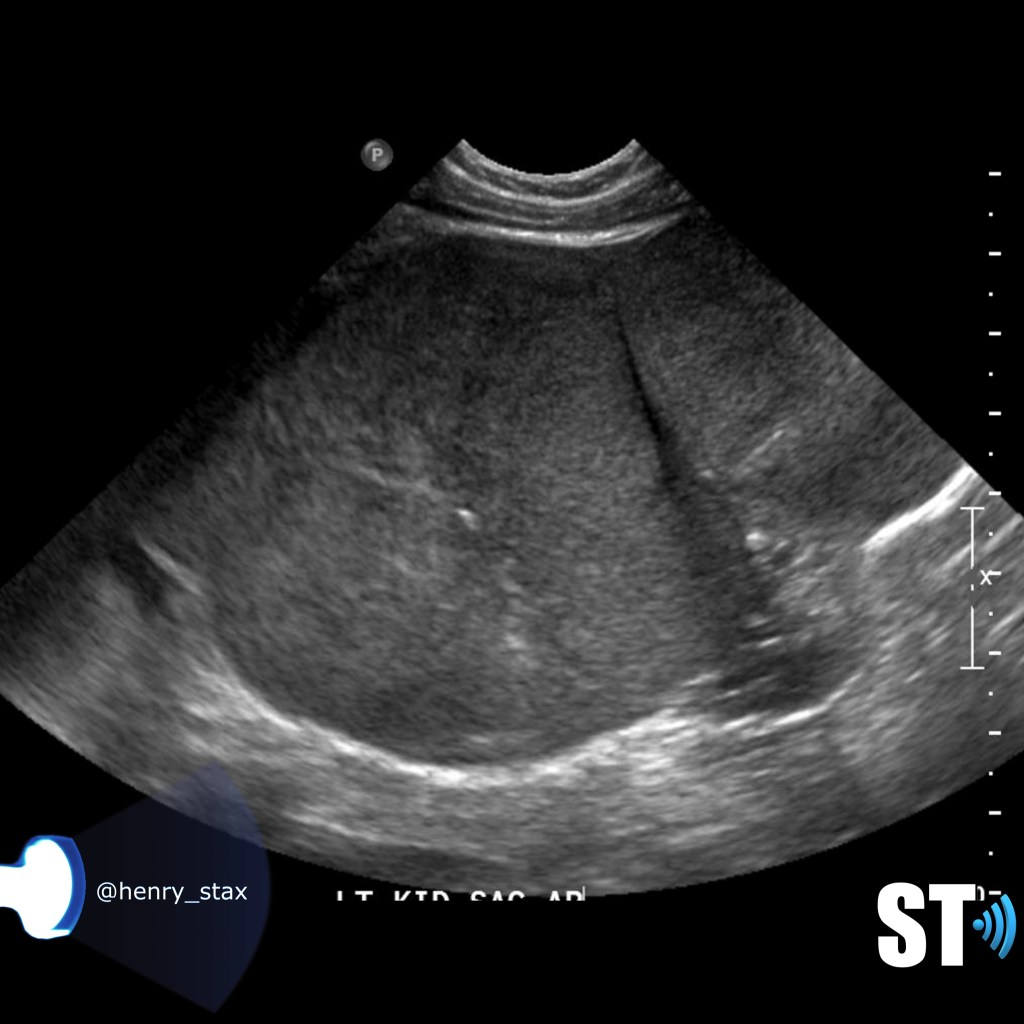

Renal Trauma

Renal trauma accounts for approximately 1-5% of all trauma admissions and as many as 10% of patients who sustain abdominal trauma. Injuries can range from contusions to life threatening injury. The types of trauma include penetrating (gsw, knife), blunt force (mva, sports injury), post procedure etc..

Patients may have abdominal/flank pain on the affected side, hematuria may also be present.